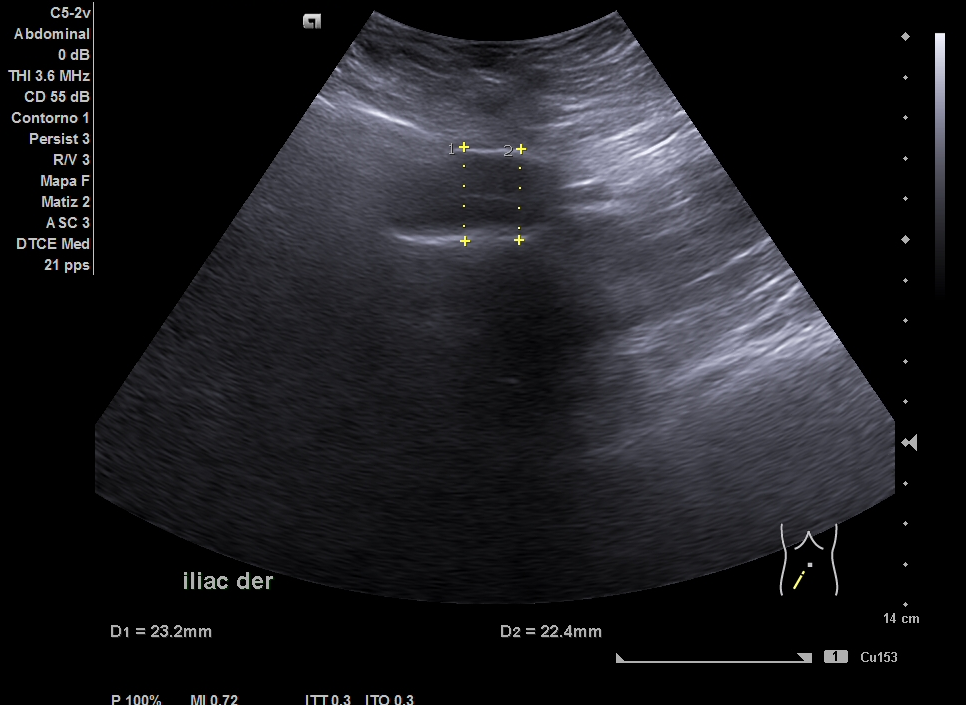

Parenquima hepatico sin alteraciones, vesícula biliar sin imagenes hiperecoénicas en interior. Pancreas visible en parte, sin alteraciones. Asimetría entre ambos riñones compatible variante de la normalidad RI. Llama la atención dilatación ilíaca derecha al comparar con contralateral y con aorta abdominal distal. Compatible con dilatación aneurismática ilíaca derecha.

Abdominalgia en estudio + Dilatación aneurismática ilíaca derecha.

El diagnóstico diferencial del Aneurisma Ilíaca con: Displasia fibromuscular u otra patología del tejido conectivo, lúes o tuberculosis entre otros. Toda dilatación que sobrepase el 50% del diámetro del vaso se considera aneurismática. Por la edad no se plantea el origen ateromatoso.